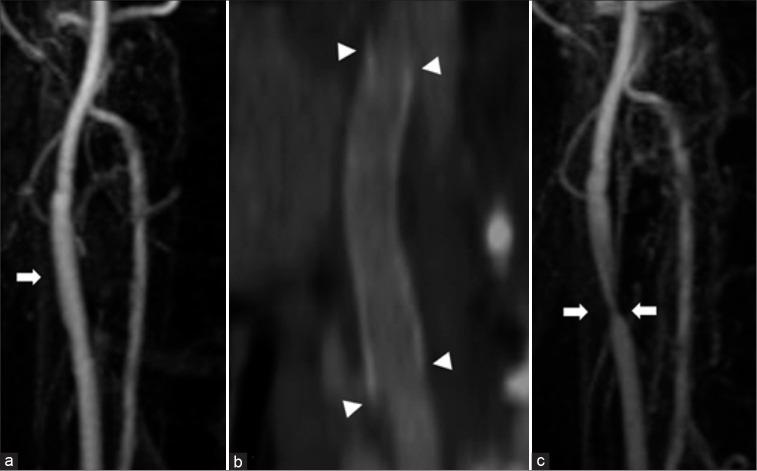

A woman in her 20s experienced injury to the right carotid artery during an operation for removal of a carotid body tumor 6 years before presentation. The right common carotid artery and internal carotid artery were replaced with an artificial vessel graft at that time. Intraluminal stenosis in the graft was not identified 3 years after surgery; however, 4 years after surgery, stenosis was recognized at the non-anastomotic site inside the artificial vessel graft. Subsequently, antiplatelet therapy was initiated. The stenosis was noted to progress gradually in follow-up appointments. Therefore, we decided to intervene because of the patient's young age and the risk of long-term hemodynamic stress. Angiography revealed pseudo-occlusion in the artificial vessel. Percutaneous transluminal angioplasty was performed for stenosis with distal protection; subsequently, CAS was performed. The patient was discharged without neurological deficits 4 days after the operation, and no apparent restenosis was observed as of the 1-year follow-up.